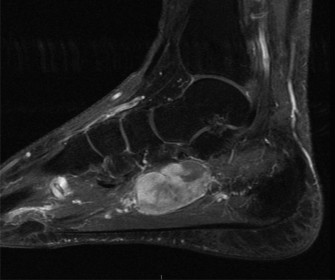

Figure 2: Coronal T1-weighted MRI image from the same patient, highlighting the comminution of the talar neck and body, and involvement of the subtalar joint. The image further elucidates the articular damage and subchondral bone changes not fully appreciated on plain radiographs or CT.

- Articular Cartilage Assessment: While CT shows bone, MRI sagittal views exquisitely demonstrate the integrity of the articular cartilage. We observed areas of chondral bruising and early subchondral edema on the talar dome, consistent with impaction. Furthermore, articular step-offs and incongruity in both the tibiotalar and subtalar joints were precisely quantified, guiding the need for meticulous anatomical reduction.

- Talar Head and Neck Morphology: The sagittal images provided a detailed profile of the fracture lines through the talar neck and body, allowing for precise measurement of anterior, posterior, and superior displacement and angulation. This was critical for understanding the extent of shortening and the specific vector required for reduction. They also helped identify small, non-displaced fracture lines or occult fractures that might be missed on CT, particularly in areas of complex anatomy.

- Subtalar Joint Involvement: The sagittal plane is paramount for evaluating the posterior facet of the subtalar joint. In our patient, the fracture clearly extended into this joint, with significant displacement of the posterior talar facet, highlighting the necessity for accurate reduction of this weight-bearing surface to prevent post-traumatic arthrosis.